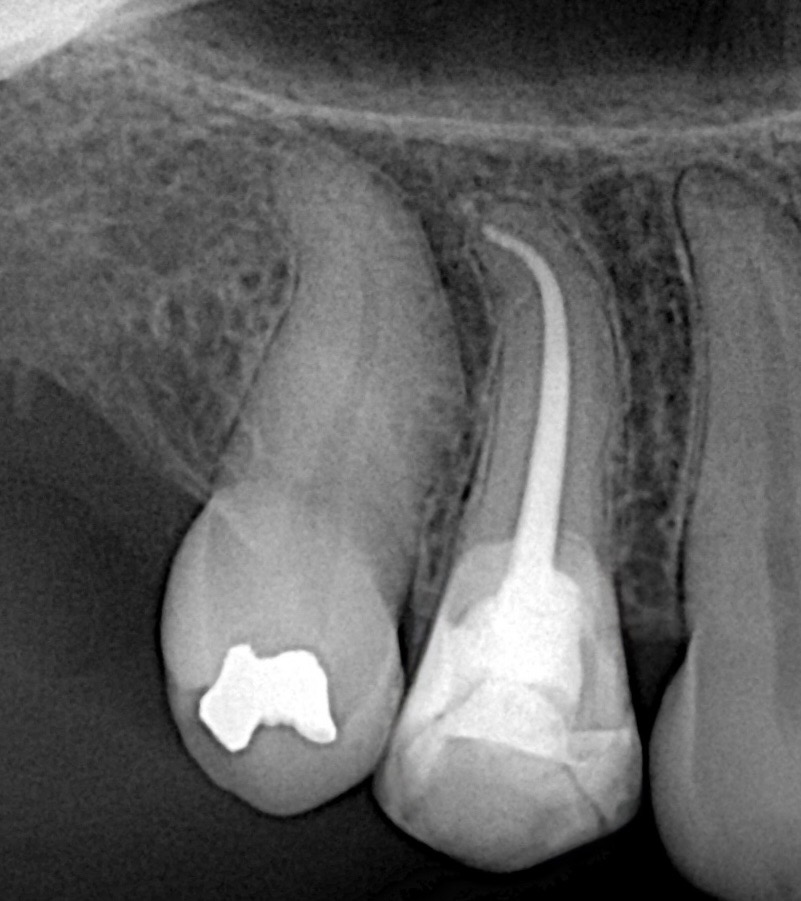

This case demonstrates the complete management of a maxillary premolar with irreversible pulpitis and compromised coronal structure. The treatment involved root canal therapy under rubber dam isolation, followed by adhesive restoration to ensure functional and esthetic rehabilitation.

5. Obturation

6. Adhesive Restoration

7. Final Outcome